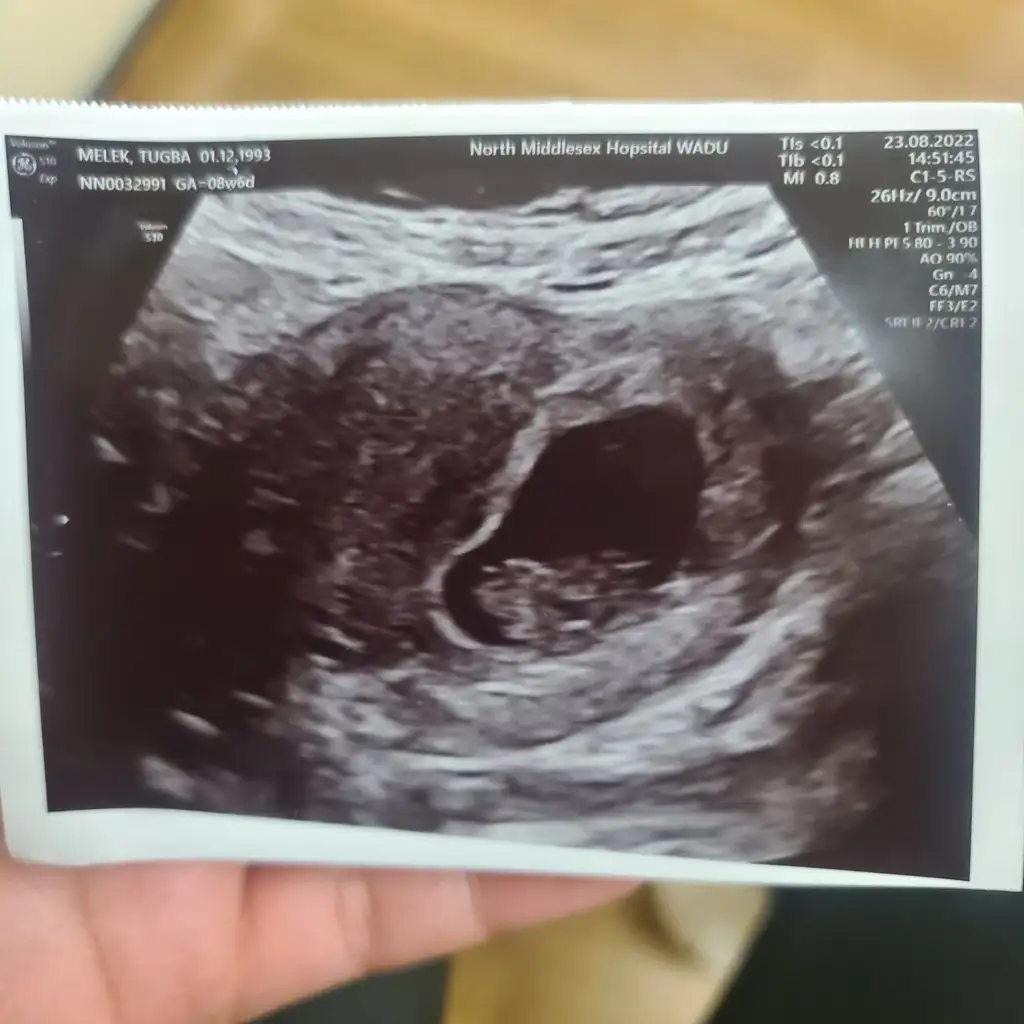

Banada bakarmısın canım hepside ultrason ile karından bakıldıSelam Kızlarbir çok kişi gruplardan beni bilir. Yine yetiştim imdatlara

Bende tahmin istiyorum lütfeeeeenayyy hadi bakalımgönlünden geçen olur inşallah haber vermeyi unutma kuzum olur mu